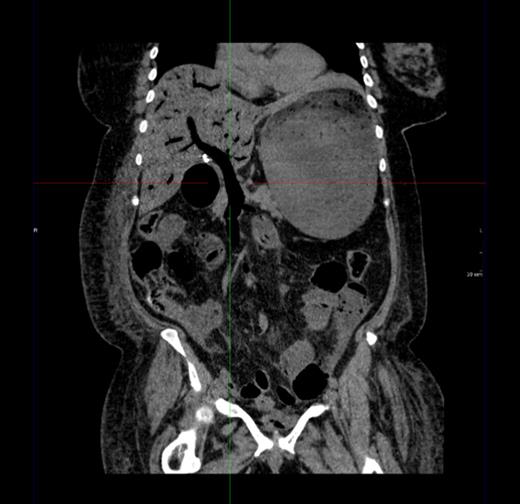

Figure 1 shows a remarkable amount of air in the hepatic portal venous system. Figure 2 demonstrates how the portal vein, splenic vein, superior mesenteric vein and its branches were all outlined with air. Figure 3 shows air within the wall of both small and large bowels. Overall, the radiological findings were suggestive of extensive bowel ischaemia.

Coronal image showing air outlining the portal vein and superior mesenteric vein.